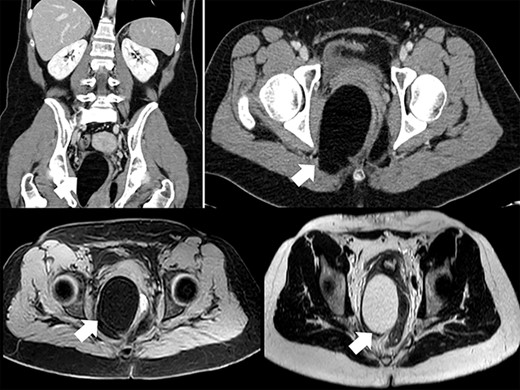

Ultrasonography detected a large pelvic mass which was confirmed by computed tomography (CT) and magnetic resonance imaging (MRI) (Fig. 1), and identified as an 8 × 5.5 cm lipoma with dislocation of the vagina, rectum and distal sigmoid colon.

MRI and CT showed no evidence of pathological nodes and the mesorectal mass was described as an asymmetrical representation of adipose tissue of the ischiorectal fossas, prevalent on the right, with dislocation to the left of the vagina, rectum and distal sigma and scarce free fluid in the pouch of Douglas. No evidence of ureteral dilation was reported at the CT-scan and renal function was not impaired (serum creatinine was 0.71 mg/dl and estimated glomerular filtration rate was 119 ml/min).

No management guidelines are currently available. CT and MRI are the gold standard for diagnosis. CT can show a homogeneously iso-intense mass with fat and no enhancement after intravenous contrast administration. MRI also enables precise diagnosis of the tumor and visualization of adjacent anatomic structures. Fat tissue demonstrates a short T1 and a relatively long T2 relaxation appearing hyperintense on T1-weighted images. Differential diagnosis between a benign and malignant lesion is not always possible without histological examination, but preoperative eco-guided biopsy has the risk of seeding the tumor. The more centrally and deeper a fatty mass is located, the more it is likely to be malignant [2]. The most indicative CT findings for malignancy are thick intralesional septa (>2 mm), rapid growth and solid components [13, 14]. Positron emission tomography has been proposed to differentiate liposarcoma, although it seems to be inadequate for differential diagnosis [2].